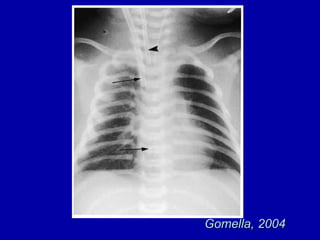

TTN

X-ray- TTNB

 X-Ray findings

– Prominent Perihilar streaking

– Hyperinflation

– Fluid in fissure